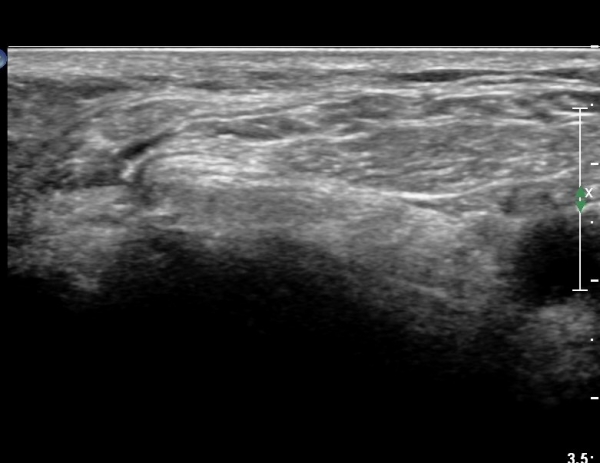

ŽÃËÀÚ¸¦ ¸»´ÜÀ¸·Î À̵¿ÇÏ´Ï À̵ιڱ٠³»Ãø¿¡¼­ ºñ°ñ½Å°æ¿Í °üÂûµÈ´Ù(»çÁø 2).